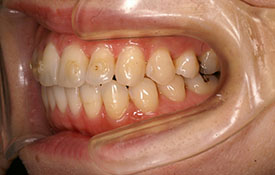

インビザラインの治療例:CASE-2

| プロフィール | 15歳 男性 |

|---|---|

| 所見 | アメリカから転院されて来られた方です。 インビザラインで上下顎の矯正治療を開始し下顎はアメリカで終了しており、上顎のみ治療の後期を担当しました。 アイライナーの装着は、1日平均22時間ほどでした。 |